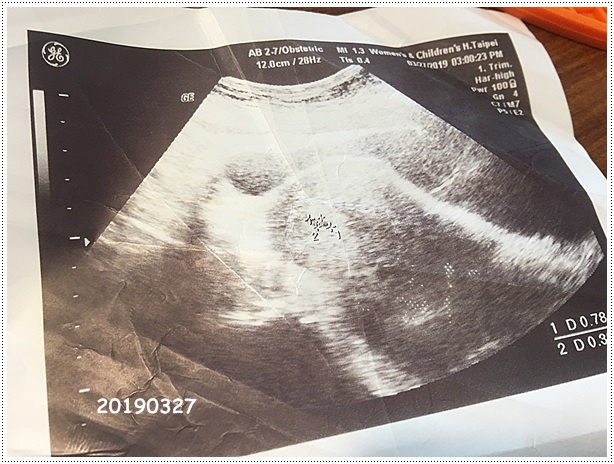

20190327

回去想想,還是想盡早確認,因為我搞不清楚上次月經來的時間,無法推知寶寶到底幾周,要是4W照不到,我還沒那麼擔心,但萬一已經5或6W了怎麼辦,左思右想,禮拜三還是請了一個小時的假,跑去掛婦幼下午鍾佳倫醫生的診,因為Greg還來不及趕過來,所以這算是我自己第一次看產科,看診前有一百個擔心,還好鍾醫生很親切,不斷跟我閒話家常順便問診,還一直安撫我不要緊張,結果照腹部超音波的時候,立馬就照到胚胎,呼!!!!!真的鬆了好大一口氣,眼淚差點要奪眶而出,媽媽很脆弱的,寶寶不要嚇我好嗎

確認懷孕位置正確,因為要出國的關係,怕身體不穩定,順便請醫生幫我開不適航證明,如果真的不舒服就不飛了,等待批價的時候,拿著寶寶的照片看啊看,順便等姍姍來遲的Greg

小小寶貝,還不到一公分,拜託拜託,你要乖乖長大喔